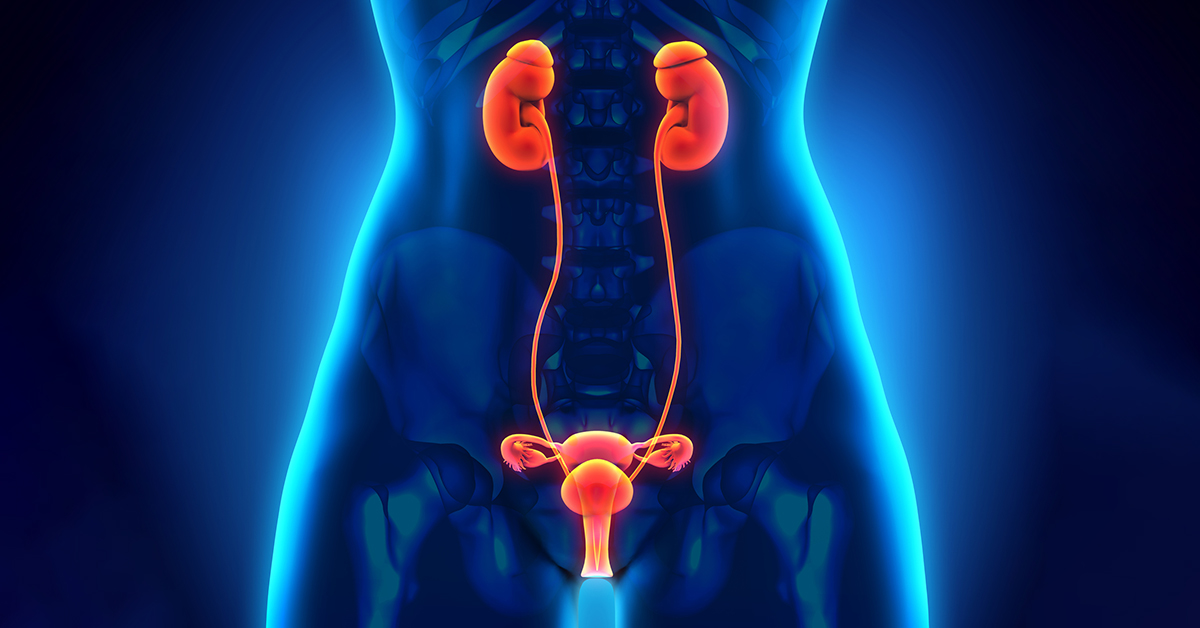

"I had an excellent experience at the urology clinic. The staff was very friendly and professional, and the doctor was knowledgeable and thorough in their examination. I received the care and attention I needed to address my urological concerns, and I highly recommend this clinic to anyone seeking quality